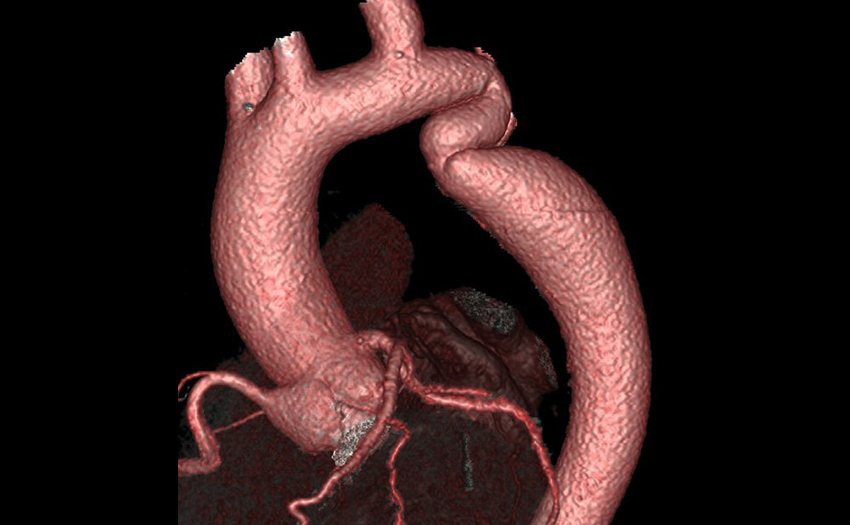

- Cardiac CT: Full Cardiac and Cardiovascular CT training on 256 slice GE Revolution scanner. Including Coronary CTA, Vascular CTA and preoperative structural CT imaging for transcatheter intervention planning.